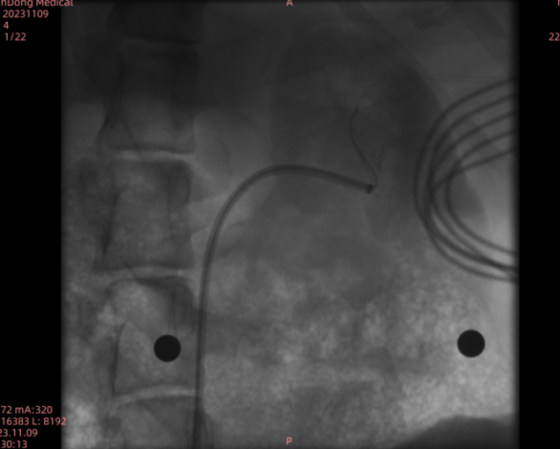

(1)血管穿刺与造影:深度麻醉后,左右侧股动脉穿刺并植入鞘管,清洗并连接导引导管及相关设备,送入体内进行DSA造影,获取术前影像资料。

(2)FBG导管测量(正常血管):清洗长鞘、导引导管等设备,送入体内至左侧肾动脉上支。嵌套微导丝、FBG导管,交替推进至目标血管后,进行FBG传感器实验测量,收集数据。